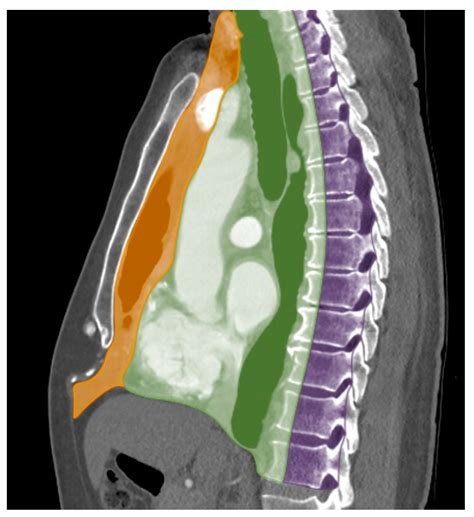

To grasp the significance of a Mass Anterior Mediastinum, one must first understand its anatomical context. The mediastinum is divided into three sections: anterior, middle, and posterior. The anterior division, also known as the prevascular space, is the most common site for various tumors and cysts. Because this space is relatively small, even a slowly growing mass can quickly compress adjacent organs, leading to noticeable symptoms.

MRI Useful for evaluating soft tissue invasion, particularly near the heart or spinal cord.